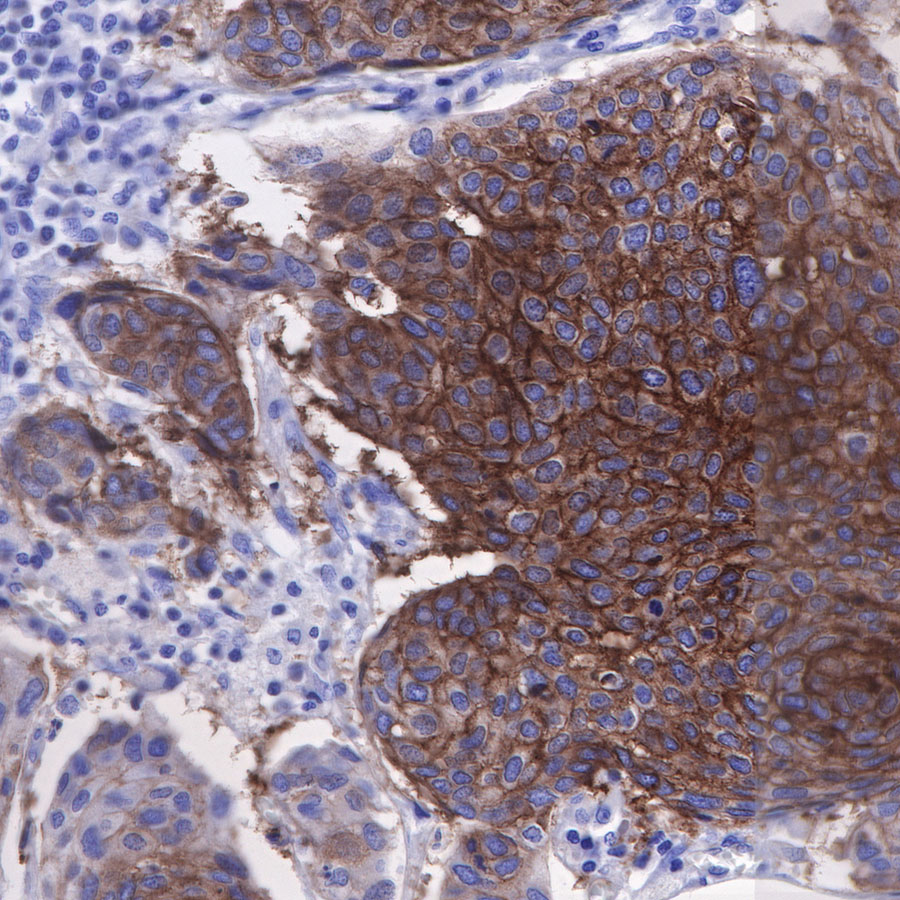

| IHC-P |

1:500 |

|